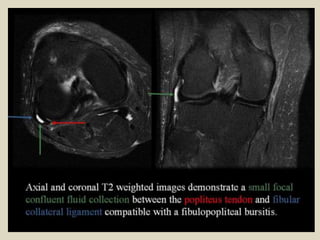

Fibular bursa. Sequential coronal fat suppressed T2WI (A) from anterior to posterior show a

multilocular cystic mass posterolateral to the iliotibial band (solid arrow), insinuating between

the fibular collateral ligament (dashed arrow) and the distal biceps femoris tendon (arrow

head), consistent with fibular bursitis. Sagittal ultrasound of the lateral knee (B) at the level of

the popliteal notch (*) demonstrates a loculated hypoechoic focus between the fibular collateral

ligament (dashed arrow) and the biceps femoris tendon (arrow heads).